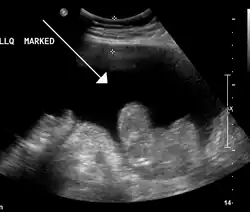

| Diagnostic method | Physical exam, ultrasound, CT scan[3] |

In the developed world, the most common cause is liver cirrhosis.[4] Other causes include cancer, heart failure, tuberculosis, pancreatitis, and blockage of the hepatic vein.[4] In cirrhosis, the underlying mechanism involves high blood pressure in the portal system and dysfunction of blood vessels.[4] Diagnosis is typically based on an examination together with ultrasound or a CT scan.[3] Testing the fluid can help in determining the underlying cause.[3]

Ultrasound investigation is often done before attempts to remove fluid from the abdomen. This may reveal the size and shape of the abdominal organs, and Doppler studies may show the direction of flow in the portal vein, as well as detecting Budd–Chiari syndrome (thrombosis of the hepatic vein) and portal vein thrombosis. The sonographer also can estimate the amount of ascitic fluid, and difficult-to-drain ascites may be drained under ultrasound guidance. An abdominal CT scan is more accurate than a sonogram to reveal abdominal organ structure and morphology.[13]